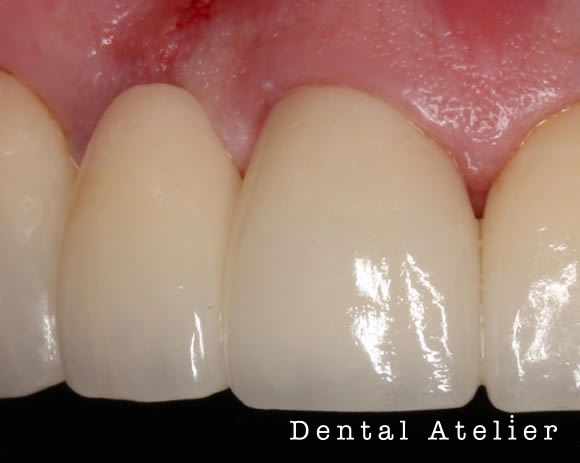

作られたセラミック歯

かぶせたセラミック歯

土台が出来上がった歯には写真のように作られた「かぶせ物(クラウン)」が入りますので、かぶせ物をセットして治療が終了します。

その土台の内部にグラスファイバー繊維(ファイバーコア・ポスト)を使うことで、歯を補強し、破折(歯が割れない・折れない)ようにするのがファイバーを使った支台築造です。

当院で行う支台築造はラバーダムを使用し細菌感染をなくし、歯に精密に埋めることで歯とファイバーが一体化し、歯への負担を減らすことが可能となります。

精度の高い支台築造を提供できます。